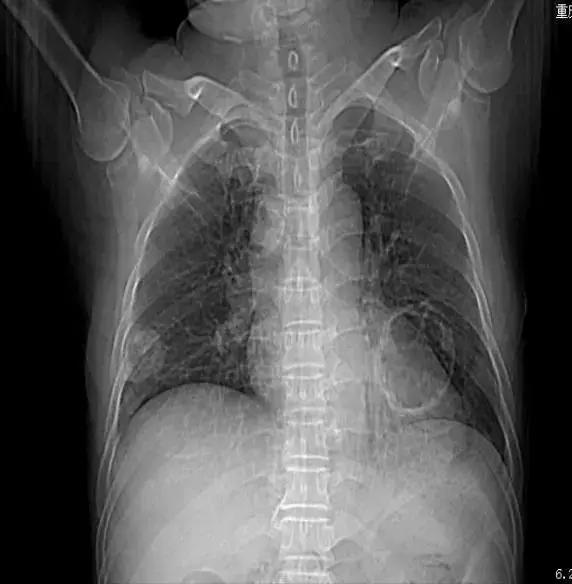

入院前胸片(当地上级医院2015-5-3)